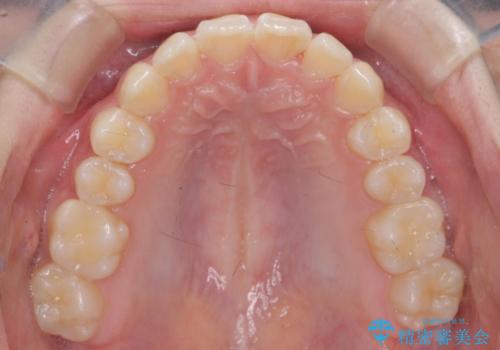

子供の出っ歯 生え代わりと成長期を利用して非抜歯で矯正

- 出っ歯を主訴に来院。

生え代わりを待ってから矯正を始めました。

特に右側のかみ合わせがずれていたため、上の奥歯を後ろに下げています。

下顎も前方に成長し、前歯のかみ合わせも同時に深かったのを浅くすることができました。